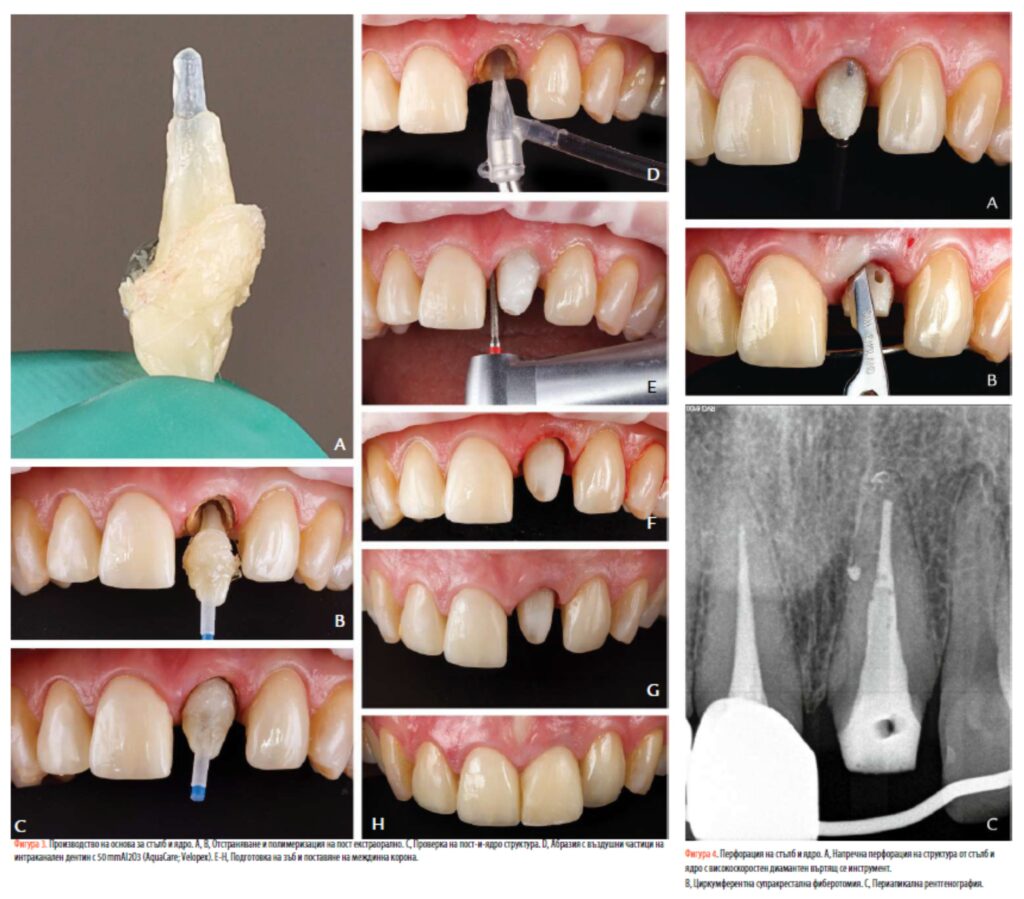

екструзия. При локална анестезия кариозният дентин беше отстранен с борер от волфрамов карбид (H1.204.014; Komet). Оперативното поле беше изолирано с помощта на бариера (OptraDam; Ivoclar AG) и политетрафлуороетиленова (PTFE) лента, поставена като изместваща връв в сулкуса (фиг. 2B). Оптичен стълб (Blue X-Post #3; Dentsply Sirona) беше маркиран, намален до подходяща дължина с високоскоростен диамантен ротационен инструмент при водно охлаждане и абразиран с въздушни частици (AquaCare TWIN; Velopex) с 29 mm частици алуминиев оксид (Al2O3) (AquaAbrasion; Velopex) за 5 секунди (фиг. 2C). Частиците бяха отстранени с въздушна спринцовка за 5 секунди и повърхността на стълба беше почистена с 95% изопропилов алкохол и намокрена с моделираща течност (GC Corp) (фиг. 2D). Слой от глицеринов гел (K-Y лубрикантен гел; Johnson & Johnson) беше поставен вътре в кореновия канал, за да се предотврати или предотврати задържането на индивидуализирания кол с композит (Ceram.x Spectra ST. LV-A2; Dentsply Sirona). След 10-секунден цикъл на светлинна полимеризация (SmartLite Pro; Dentsply Sirona), щифтът беше отстранен и полимеризацията на композита беше завършена извън устата (фиг. 2E, 3A). Стените на дентина на кореновия канал бяха абразирани с въздушни частици за още 10 секунди с 50-mmA2lO3 (AquaCare; Velopex) и след това почистени с вода за 20 секунди. Коренните стени бяха изсушени с абсорбиращи хартиени върхове преди свързване. Prime&Bond active (Dentsply Sirona) в режим на самоецване със Self Cure Activator (Dentsply Sirona) беше приложен вътре в стените на кореновия канал за 20 секунди. Излишъкът от адхезив се отстранява с абсорбиращи хартиени накрайници и разтворителят се изпарява чрез лек въздушен поток за 5 секунди. Повърхността на композитната смола на щифта след това се активира повторно със същия протокол, използван преди, но замествайки композитната смола с адхезива за дентин, нанесен върху зъба. Циментирането на влакнест щифт и изграждането на сърцевината бяха извършени в 1 стъпка чрез нанасяне на двойно полимеризираща композитна смола (Core-X Flow; Dentsply Sirona) директно върху повърхността на влакнестия щифт и в кореновия канал (фиг. 3B-H).

Впоследствие цервикалната област на сърцевината беше перфорирана напречно с високоскоростен диамантен въртящ се инструмент (859-010; Intensiv AS), като се внимава да не се повреди влакнестият стълб (фиг. 4). Интракороналните еластични и метални лигатури бяха поставени през създадения отвор и бяха сменяни всяка седмица в продължение на 3 седмици.(24) Метален щифт с дебелина 1,5 mm беше адаптиран към палатиналните повърхности на предните зъби за закрепване на ортодонтската тракция и беше циментиран в максиларните кучешки зъби и първи премолари с композитна смола за насипно пълнене (SDR Flow; Dentsply Sirona) (фиг. 5).